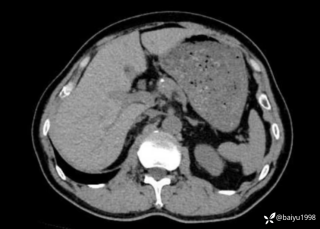

灼见|如果是你,如何处置山东男孩(多器官切除病例)

文/西地兰 特别声明:所有观点仅代表个人言论 特别声明:与当事双方均无利益相关 山东男孩,目前全网沸沸扬扬,看过一些观点,直言不讳地说,大多偏颇。要么一股脑地指责医方的全责,甚至有说千万别在县医院看病。要么又为医方无休止的遮羞,认为这样的手术在县医院做下来已经非常了不起。而我想到的是,以后面临类似的病例,我们怎么办?那么我们不如来一次专业的病案讨论。既然是事后讨论,难免有事后诸葛亮的感觉,但是假如下一次,同行们遭遇这样的病例,如何处置?这是医疗行业所面临的问题。希望我整理的这些思路和相关病例,对同行们有所帮助!就目前的资讯外界不足以判断是否需要急诊,如果需要急诊,那么只能根据术中所见进行处理,

目前知道的消息,第一,术前发现一个血肿,然后做增强CT发现一个占位,没说血肿与肿瘤的关系,术后病理没有描述肿瘤出现破裂出血,大概率就一个小血肿,我就不明白当地主任凭哪个指针去给这小孩开急诊刀的?哪个指南告诉他需要急诊开?第二,诊断不明确他想的不是进一步检查,一边观察一边进一步查,他反而选择腹腔镜探查,这个探查的指针在哪?第三,腹腔一个血肿,没有活动性出血,没有血压心率出现问题,为什么要开腹进去碰它?不能等血肿吸收再明确肿瘤性质吗?第四,1点进腹,3点病理结果出来,按这个时间还算顺利,应该还没出事,孩子还算平稳,病理是低度恶性,切了就治愈,他一年能开几台这手术,就敢继续做,拿孩子练手。第五,后面

2023年10月26日,来自山东菏泽市成武县的小烨和他家人的命运被彻底改变了。这个原本阳光、可爱的小男孩在一次意外被撞击后,在医院检查出了腹腔内存在肿瘤,并在手术中被切除了包括十二指肠、胰腺、大部分胃和小肠等多个器官。此后便无法再像正常人一样吃饭、喝水,活着要靠长期静脉注射营养液。一份2024年12月由第三方机构出具的司法鉴定意见书显示,当时给小烨做手术的成武县人民医院在该医疗行为中存在过错,与小烨的损害后果之间存在因果关系,建议医疗过错在损害后果中的原因力大小为同等原因。此外,另一份由成武县卫生健康局在2025年9月28日发出的书面答复中显示,成武县人民医院存在24小时内未完成病历;手术知情